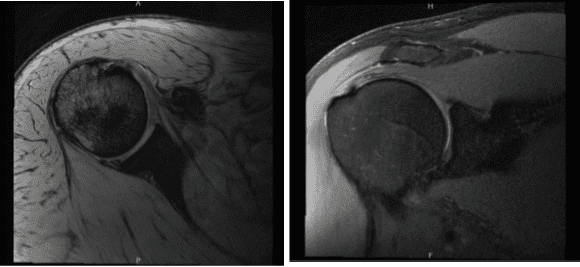

MRI were reviewed and discussed by the doctor, there is mild supraspinatus and infraspinatus tendinosis. Mild subscapularis tendinosis is present with a focal partial-thickness tear of the mid fibers.

A small lobulated hyperintense focus along the superficial margin of the subscapularis tendon likely reflects a small ganglion. The tree’s minor tendon is intact. No full-thickness rotator cuff tear is identified. No disproportionate rotator cuff muscle atrophy is present.

There is mild acromioclavicular joint arthrosis. Mild subacromial-subdeltoid bursitis is present. It showed that it has partial tearing of the rotator cuff as well as tear of the biceps tendon along with subacromial spur and AC arthritis. The biceps tendon is located within the bicipital groove.

There is mild biceps tendinosis, preferentially of its intra-articular portion, with a linear partial-thickness tear of the intra-articular portion of the bicep’s tendon extending distally to the level of the proximal bicipital groove. Minimal biceps tenosynovitis is present

There is a tear of the superior labrum which extends into the anterior superior and posterosuperior labrum. No focal chondral defect is identified over the glenohumeral joint. Trace fluid is present within the glenohumeral joint. There is no acute fracture or osteonecrosis.

Mild multifocal rotator cuff tendinosis with a focal partial-thickness tear of the subscapularis tendon. No full-thickness rotator cuff tear. Linear partial-thickness tear of the intra-articular portion of the bicep’s tendon extending distally to the level of the proximal bicipital groove, superimposed on mild tendinosis, with minimal biceps tenosynovitis.

Tear of the superior labrum which extends into the anterior superior and posterosuperior labrum. Mild acromioclavicular joint arthrosis. Mild subacromial-subdeltoid bursitis.

MRI-3T Right shoulder non-contrast